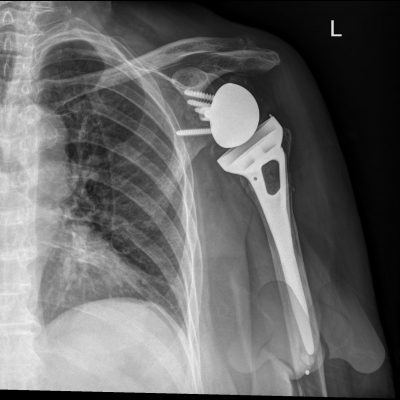

Anatomic total shoulder replacement replaces the ball and socket in their usual position. The bone and cartilage surfaces are removed and replaced with metal, plastic, ceramic or pyrocarbon surfaces. This provides pain free restoration of movement in most cases.

Reverse Total Shoulder Replacement replaces the ball and socket in a reverse configuration. This is where the artificial ball is attached to the shoulder blade and the socket is positioned onto the top of the arm. Reversing the joint parts allows the deltoid muscle to now drive shoulder movement and take over the role of the torn rotator cuff.